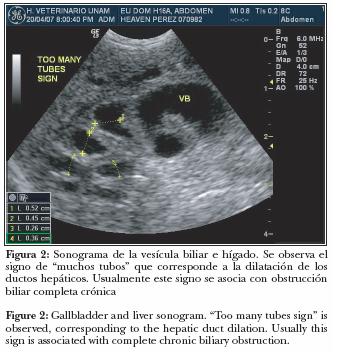

La gata fue hospitalizada, se canalizó con solución Ringer a terapia de mantenimiento y 9% deshidratación (DH), medicada con tramadol a 2 mg/kg IV TID, alimento forzado con dieta baja en grasas y alta en calorías. Se realizó estudio radiográfico simple de abdomen donde se observaron estructuras radiopacas de 0.5 a 1.0 cm de diámetro, con densidad mineral localizadas en abdomen craneal, entre el 10, 11 y 12 espacios intercostales, correspondiendo anatómicamente a la vesícula biliar. Uno de los cálculos se localizó caudal a la silueta gástrica (Figura 1). En el ultrasonido de abdomen, la vesícula biliar se encontró severamente dilatada, con abundante lodo y múltiples cálculos. También se observaron múltiples estructuras tubulares anecoicas que corresponden al llamado "signo de muchos tubos", asociado con dilatación de los ductos hepáticos (Figura 2).

Para visualizar cálculos en una radiografía simple, éstos deben tener al calcio como componente principal. Un análisis de colelitos en perros y gatos, por cristalografía, mostró que están formados por 40% de carbonato de calcio, 55% de bilirrubinato de calcio y sólo 5% de colesterol.8 Por ello se deduce que 50% se diagnostican mediante estudio radiográfico simple. Sin embargo, en medicina humana sólo 16% a 32% de los cálculos biliares se muestran como opacidades visibles en la radiografía simple de abdomen, ya que en su mayoría la composición es de colesterol.8 En este caso, el diagnóstico de ultrasonido no sólo corroboró la presencia de cálculos biliares observados en el estudio radiográfico simple, sino que evidenció dilatación de vesícula biliar, obstrucción del colédoco y dilatación de ductos hepáticos.